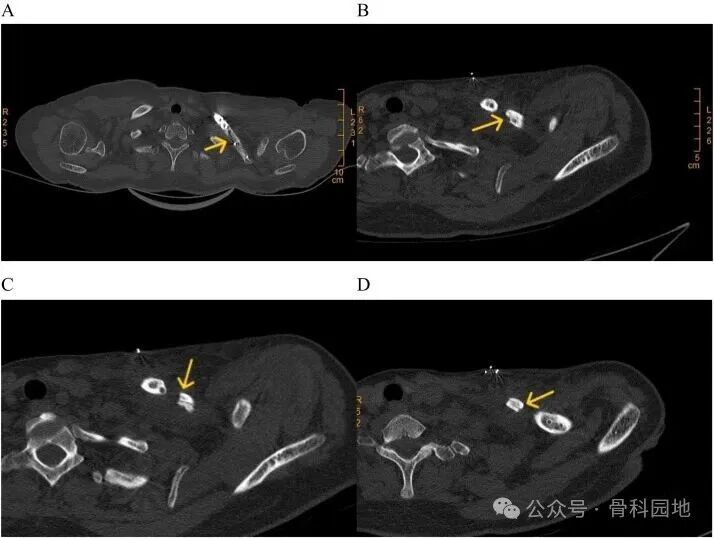

A. 术前影像、B. 术后影像:显示内固定已到位。C. 术后4个月:骨折线仍然清晰可见,表明骨折愈合延迟。D.术后11个月:骨折线依然可见。E. 术后17个月:未见明显骨折线,通常说明骨折已愈合。F. 内固定移除后:骨折端移位,骨折发生了。G. 2次手术后。

1. 术后11个月随访的X光和CT显示骨折未愈合,表明患者骨折延迟愈合, 间接表明骨折末端血液供应不足及骨质恢复缓慢;

2. 骨片螺钉位于锁骨狭窄的中间部分,骨折部位后缘有明显的骨缺损,使锁骨中部本已薄弱的部分更加脆弱。